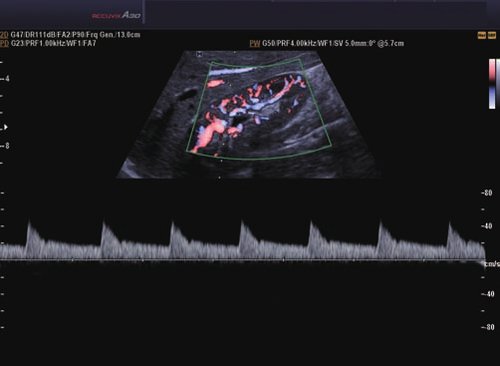

• Farb-Doppler

• Pulsed Wave (PW)-Spektral-Doppler

• Continuous Wave (CW)-Doppler

• Color Opt Flow™ bietet kraftvollere Farben und verbessert die Bildqualität.